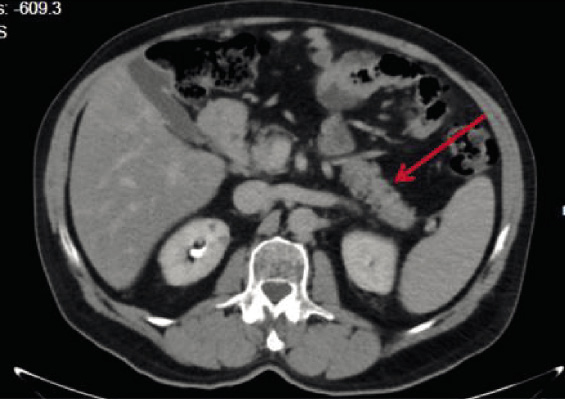

Figure 5. Contrast-enhanced abdominal CT scan in October 2020 showed normal pancreas (red arrow).

The most recent laboratory tests, performed in November 2020 (Tables II), detected serum amylase = 141 U/L (nv <100 U/L) and serum lipase = 402 U/L (nv <60 U/L). The contrast-enhanced abdominal CT showed normal pancreas, unchanged liver, and kidney cysts (Figure 5).